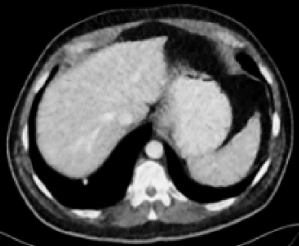

| RED-CNN+SSWL (0.8901) | RVAE (0.8851) | RVAE+SSWL (0.9023) |

Figs. 3 and 4 demonstrate precise removal of noise from whole scans as well as specific regions of interest (ROIs), proving the effectiveness of our model over baseline architectures and other self-supervised tasks. As shown, both the RVAE and SSWL are able to quantitatively and qualitatively outperform their respective counterparts.